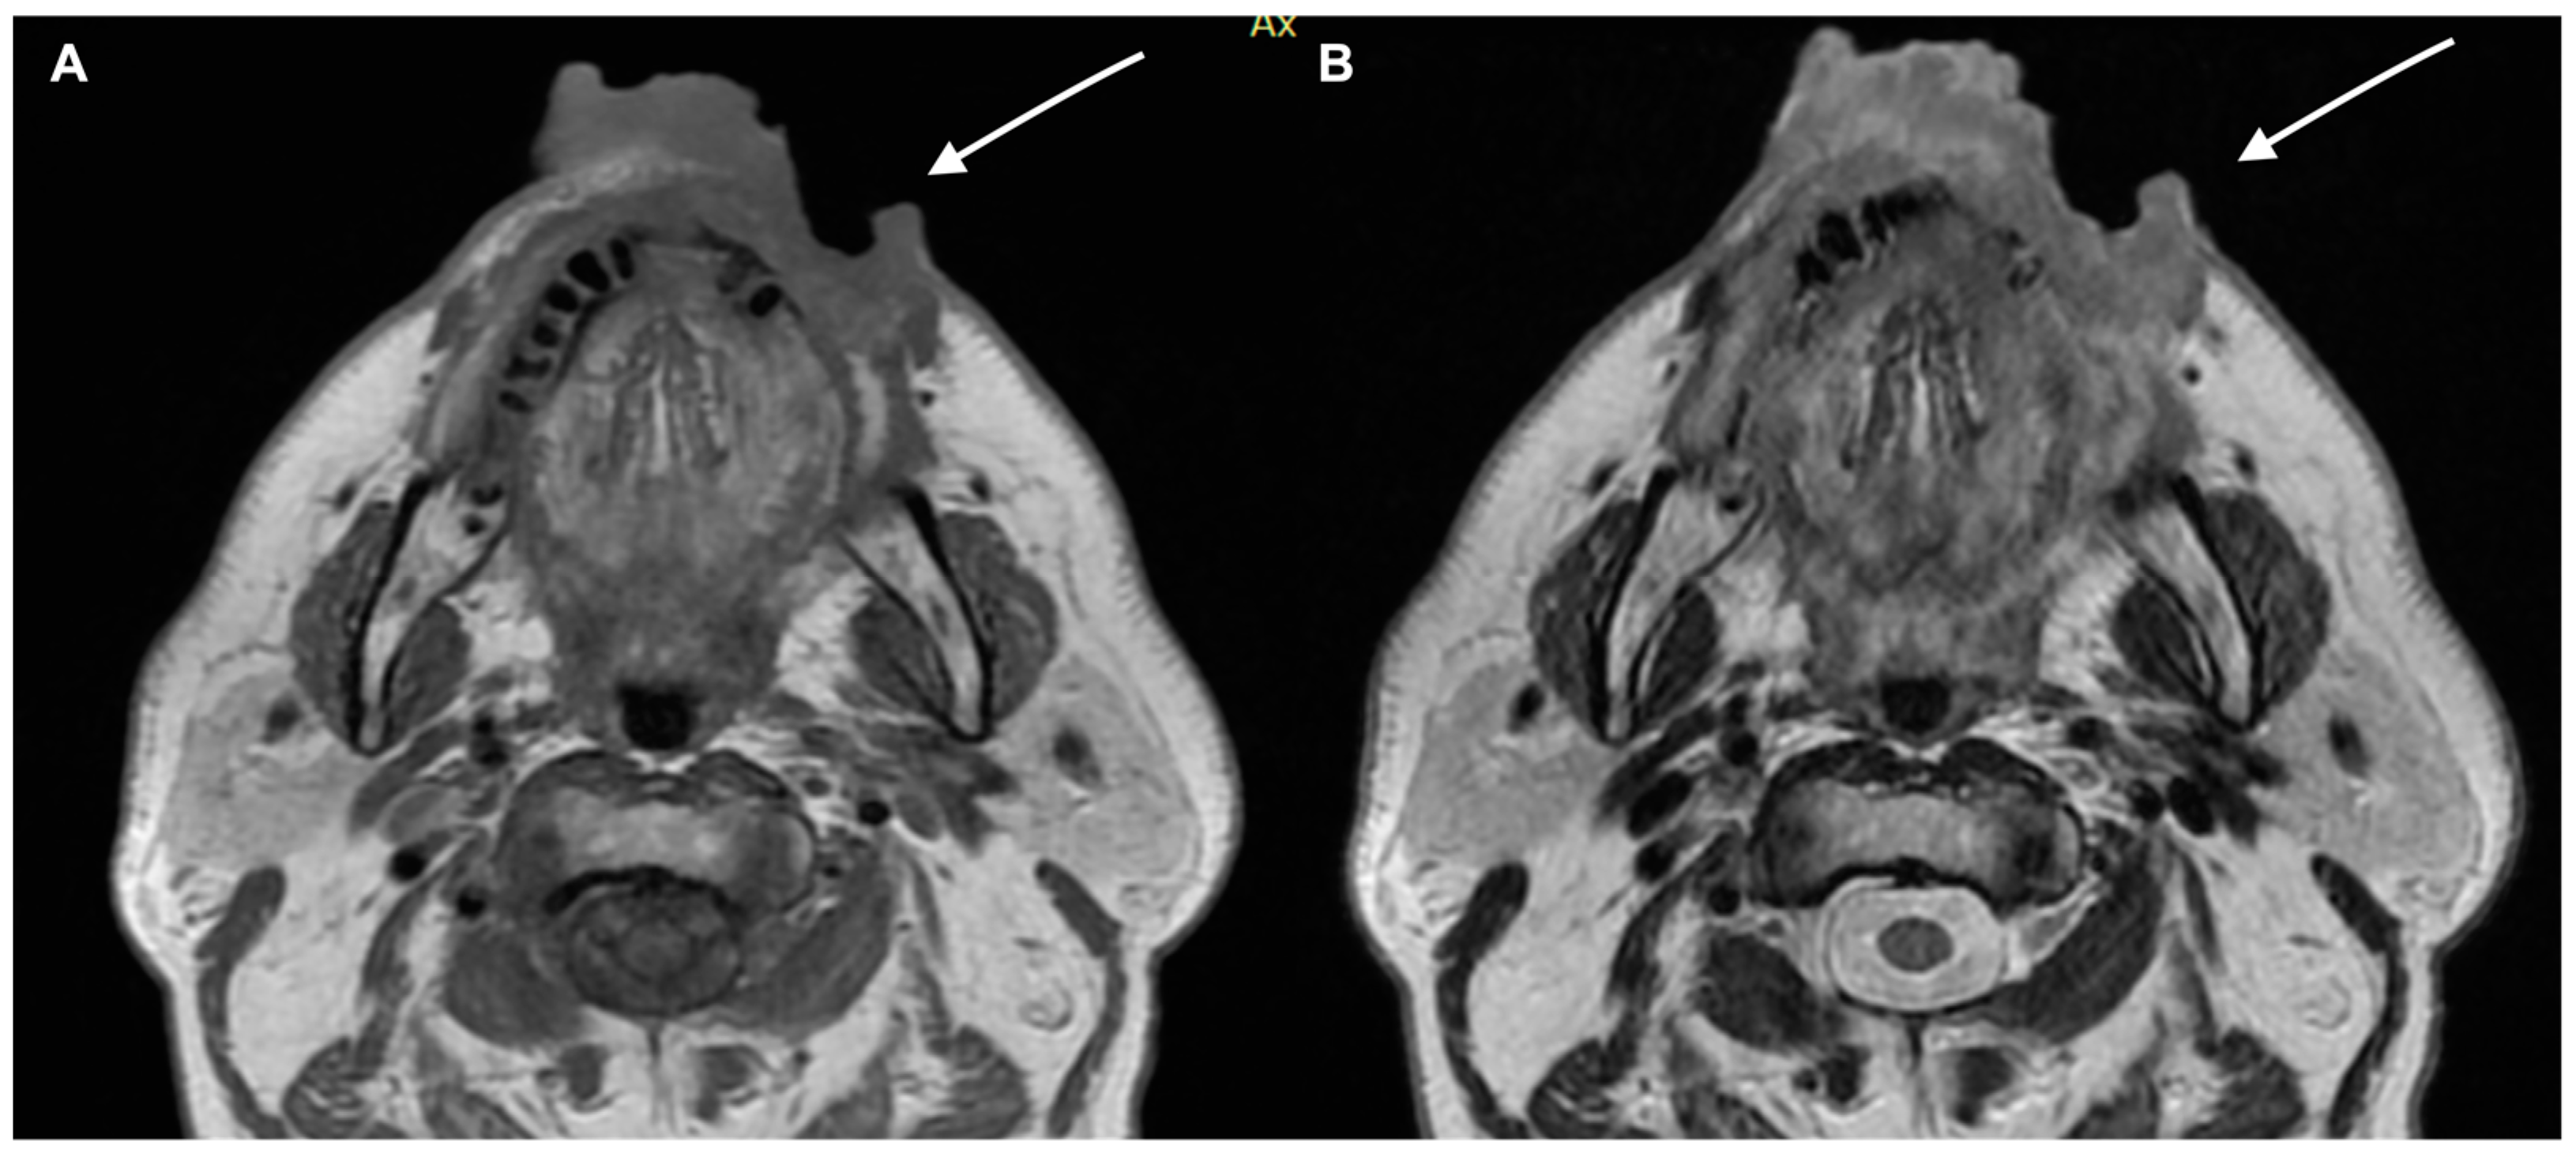

2. Diagnostic Imaging and Non-Melanoma Skin Cancer

3. Diagnostic Tools and Non-Melanoma: Staging and Surveillance